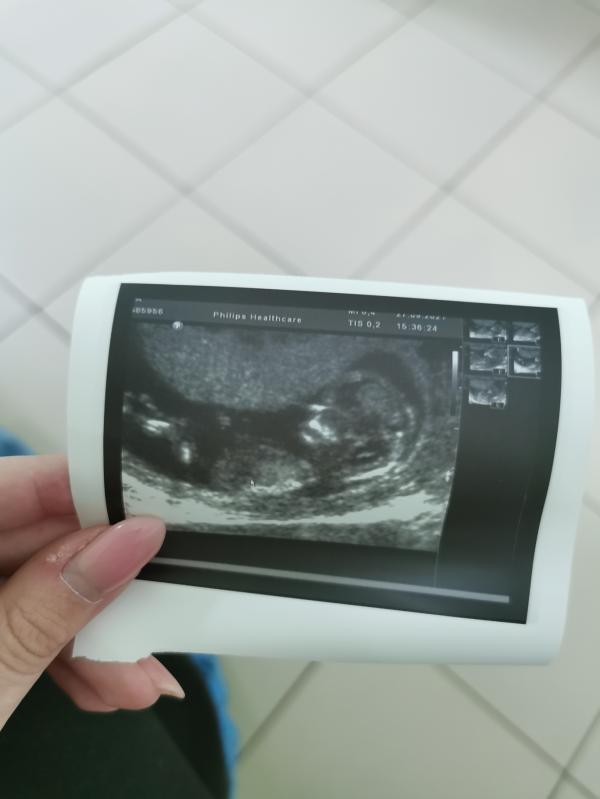

Всем привет , первый скрининг прошёл отлично 😍

Сказали , что модель у меня в животе юнная , с длинными ногами )

Пол сказали сразу , все показала , не скрывала )

Тоже когда пол сказали предполагаемый на первом скрининге, решили ещё раз уже точно убедится и сходить узнать пол на 17 неделе , подтвердили , теперь ждём девочку 😊